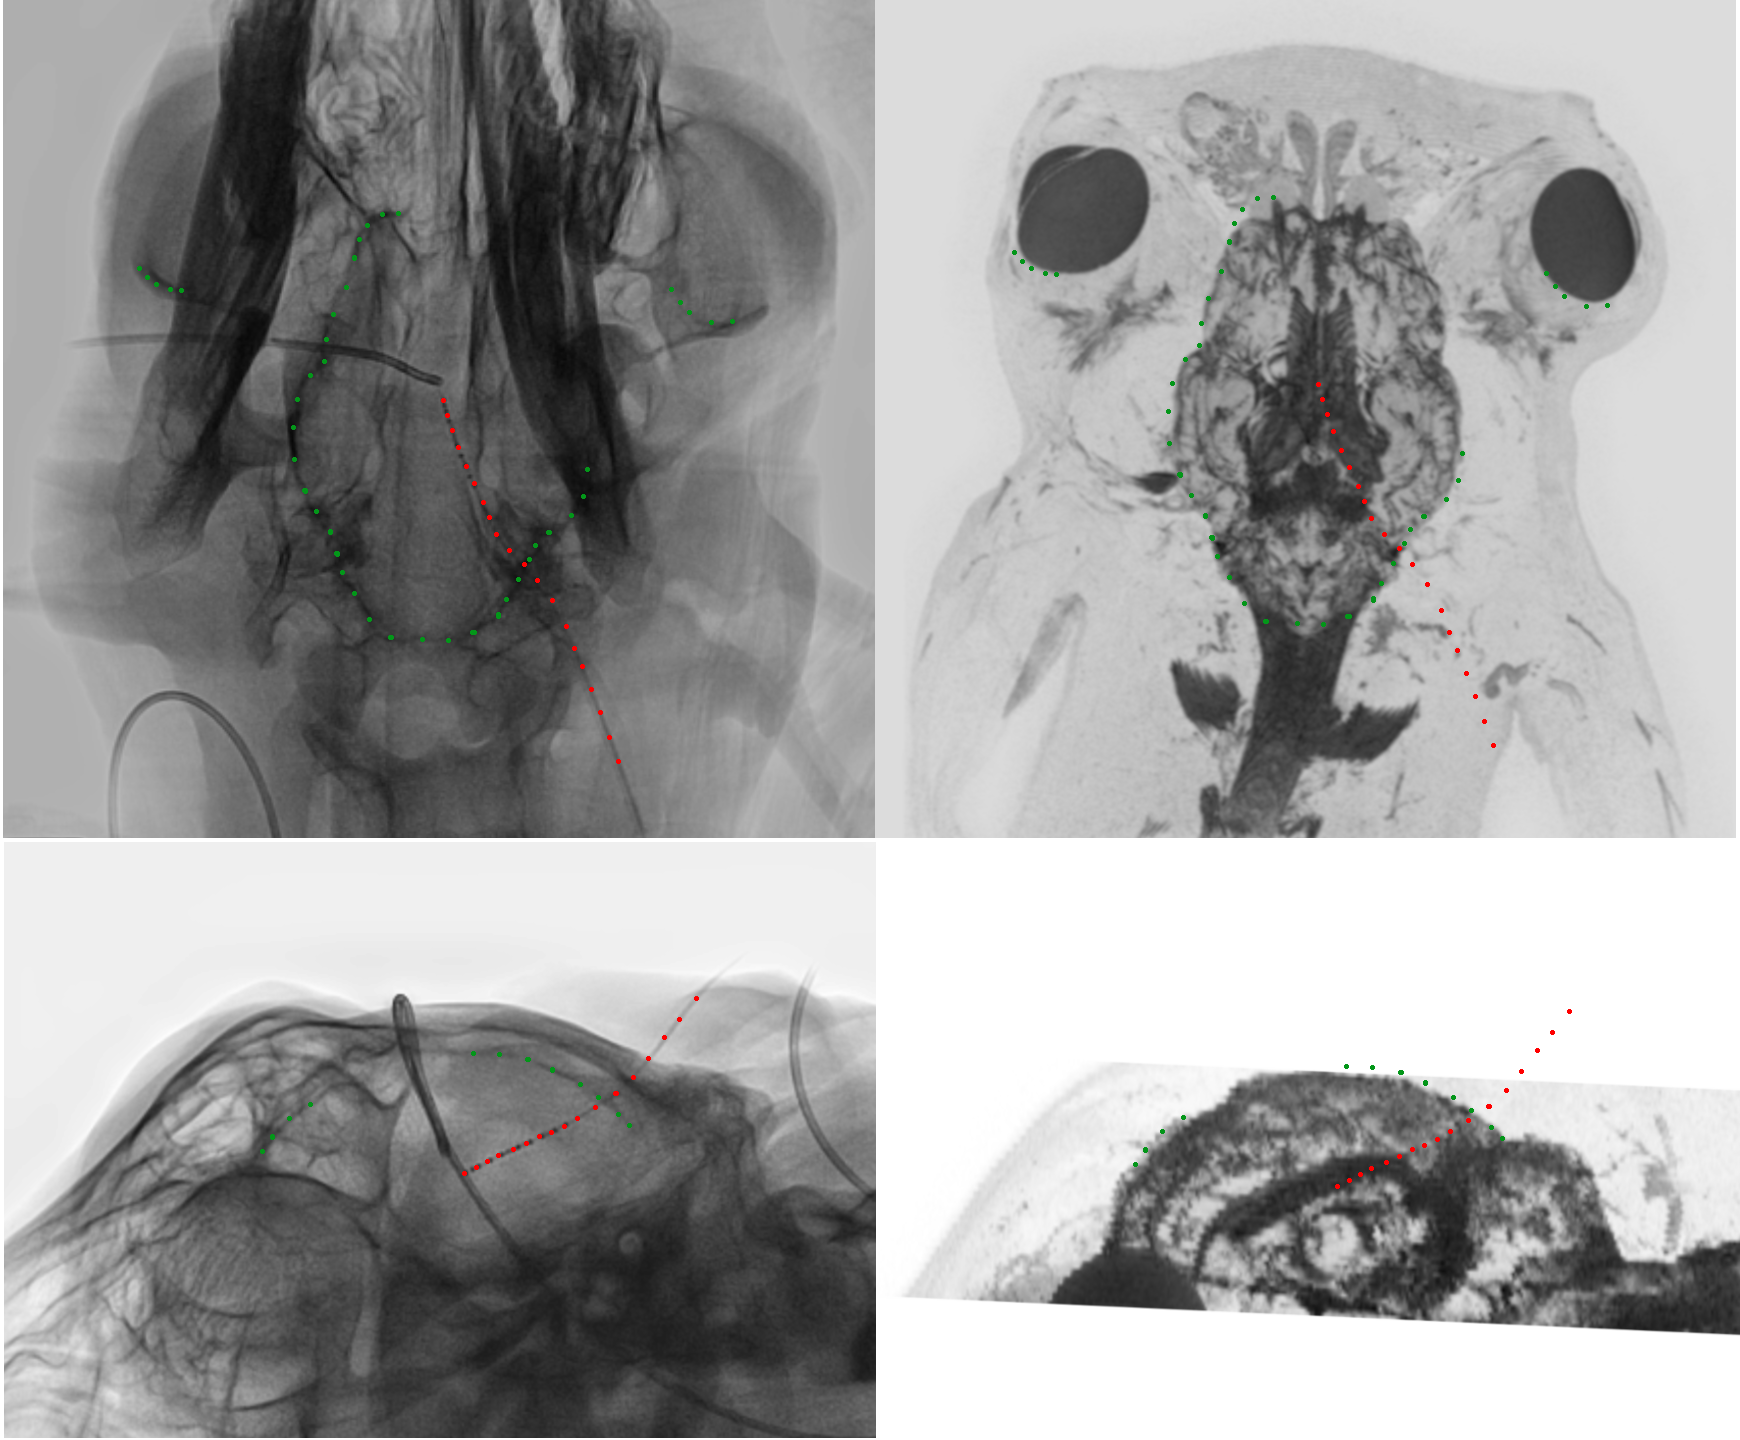

A small frontal burr hole trephination was performed using a diamond drill to access the sheep’s left lateral ventricle and insert the measurement catheter for ICP and BI. A bone wax plug (Ethicon Bone wax, Johnson & Johnson Medical Ltd., Livingston, United Kingdom) was molded around the exiting catheter to seal the burr hole in the cranium, thus ensuring proper fixation and preventing leakage of CSF or alterations in ICP. A \qty4.5 spinal catheter (Neuromedex, Hamburg, Germany) was placed in the intrathecal sac via a laminotomy at level L6-7 to measure intrathecal pressure (ITP). The same access was used for the placement of a spinal needle (Perifix 310 mini set, \qty5, B.Braun Melsungen AG, Melsungen, Germany) to perform infusion experiments. Similar to the cranial access, the catheter and needle were again secured using bone wax. Intravascular catheters (Avanti, Cordis Corporation, Miami Lakes, FL, United States) were placed in the carotid artery and jugular vein to measure arterial blood pressure (ABP) and central venous pressure (CVP), respectively. Medical pressure transducers (Meritrans DTXPlus, Merit Medical Systems, Jordan, UT, United States) were used for the measurement of ABP, CVP and ITP, whereas ICP and BI were acquired with the custom-built measurement system described in Section 2.1.1. All signals were sampled with a frequency of \qty1\kilo and recorded using an embedded real-time computer (MicroLabBox, dSpace GmbH, Paderborn, Germany). The placement of the BI and ICP measurement catheter was confirmed at the end of the in vivo pilot study using fluoroscopy and magnetic resonance imaging (MRI), as shown in Figure 3.

Refer to caption

Figure 3: Confirmation of the measurement catheter placement at the end of the in vivo pilot study using both fluoroscopy and magnetic resonance imaging (MRI). Left: Transverse and coronal 2D fluoroscopy acquisitions of the head with implanted measurement catheter. Right: Re-sliced minimum intensity projection of the phase-sensitive Short-TI Inversion Recovery acquisition of the same brain following explantation of the measurement catheter. The green dotted lines indicate anatomical landmarks for co-registration of fluoroscopy and MRI data, whereas the red dotted lines show the trace of the measurement catheter.